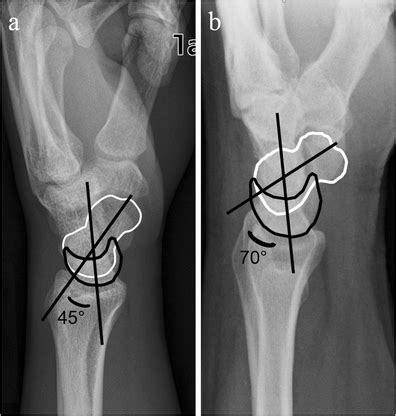

1. Increased Scapholunate Angle (SLA)

• Normal: approximately 30°–60°

• DISI: typically greater than 70°

• This is the single most quoted numeric criterion in exams

1. Increased Radiolunate Angle (RLA)

• Normal: near neutral

• DISI: greater than 10°, reflecting dorsal lunate tilt

1. Increased Capitolunate (Lunocapitate) Angle

• Normal: less than 30°

• DISI: greater than 30°, indicating loss of collinearity between lunate and capitate